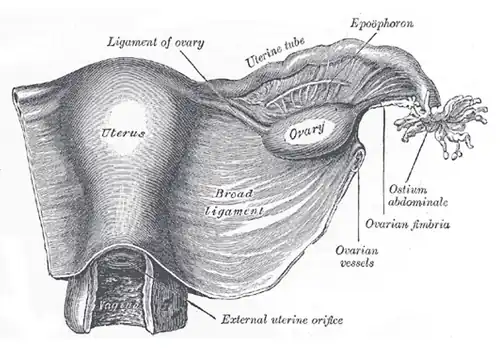

Anatomía

Existen dos oviductos, cada uno conecta un ovario con el sector superior y lateral del útero.

Se extienden a lo largo del margen superior de los ligamentos anchos del útero, desde su extremo medial o "cuernos del útero" hasta su extremo lateral en la superficie del ovario.

Cada trompa se ancla en su cara inferior, mediante una doble hoja de peritoneo llamada mesosálpinx y se abre a la cavidad peritoneal.[7][8][5][3]

Pabellón de la trompa

Porción fímbrica, embudo, extremidad ovárica o infundíbulo, es la sección con forma de embudo por la cual se conecta el oviducto con el ovario.

- Fimbrias

El pabellón posee en su borde libre unas digitaciones o flecos llamados fimbrias que parecen abrazar al ovario y palpan su superficie para determinar dónde se va a producir la ovulación.

El epitelio del pabellón está conformado por células secretoras y células ciliadas. La motilidad de estas cilias es esencial para la captación del óvulo y por tanto para la fertilidad.

Ampolla de la trompa

Porción ámpula, ampolla de la trompa es la zona dilatada de la trompa y lugar donde se produce la fecundación. Es la sección más ancha y larga con más de la mitad de la longitud total de la trompa. La ampolla sola, mide de 7 a 8 centímetros de longitud y tiene 7-8 milímetros de diámetro.

Istmo de la trompa

Porción ístmica, istmo de la trompa: es la porción de mayor longitud y también de mayor estrechez, con estructura redonda y en forma de cordón que constituye el tercio medial de la trompa. Llega a la parte superior y lateral del útero (unión útero-tubárica). Presenta menos pliegues en su mucosa y abundantes células secretoras.[6]

Intersticio de la trompa

Porción intraparietal, oviducto intramural: pequeña porción de 1 centímetro (cm) de longitud y hasta 1 milímetro (mm) de diámetro, es el segmento que atraviesa la pared del útero y lo conecta con el istmo (unión útero-tubárica).[6]